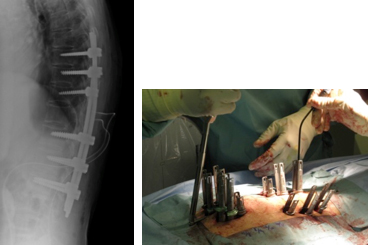

(1)胸椎に肺癌の転移性腫瘍を認めます。脳転移などもあったため、根治的手術は困難でした。

(2)経皮的椎弓根スクリューを用いた特殊な方法で、脊椎を安定化しています。

術後、麻痺の改善と疼痛の緩和を認めました。

腰の第4番目、5 番目の椎体が感染し、進行性の骨破壊と後弯変形を認めます。経皮的椎弓根スクリューを用いた特殊な方法で、脊椎を安定化しています。

(左)術前の進行性の骨破壊が見られましたが、(右)術後1年では良好な骨癒合が得られています。